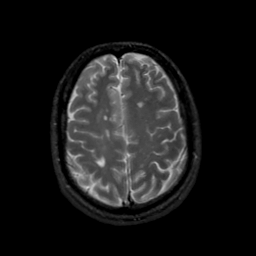

MR Study #22, December 1, 1991 -- Slice #38

[Home][Help][Clinical][Tour 1][Tour 2] Slice 38